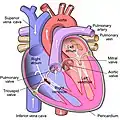

.svg.png.webp) Anterior (frontal) view of the opened heart. White arrows indicate normal blood flow. (Tricuspid valve labeled at bottom left.) | |

Heart in motion: the anterior walls of the ventricles are removed. The action of the tricuspid valve, located in the right ventricle, is seen on the left portion of this illustration. The three leaflets with their attached chordae tendineae and papillary muscles can be seen. | |

The tricuspid valve, or right atrioventricular valve, is on the right dorsal side of the mammalian heart, at the superior portion of the right ventricle. The function of the valve is to allow blood to flow from the right atrium to the right ventricle during diastole, and to close to prevent backflow (regurgitation) from the right ventricle into the right atrium during right ventricular contraction (systole).

Structure

The tricuspid valve usually has three cusps or leaflets, named the anterior, posterior, and septal cusps.[1] Each leaflet is connected via chordae tendineae to the anterior, posterior, and septal papillary muscles of the right ventricle, respectively. Tricuspid valves may also occur with two or four leaflets; the number may change over a lifetime.[2]